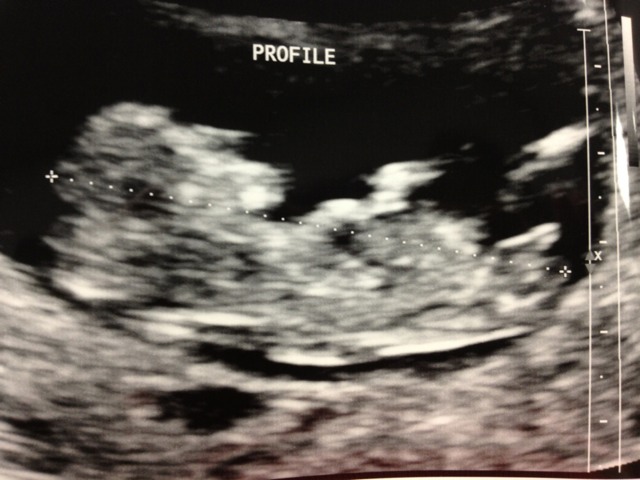

Please be honest with your guesses! I'd rather be prepared if the nub looks boyish. Baby is measuring exactly 12 0.

very boyish nub

I'm sorry to say this, but that nub looks very boyish to me.

I say boy.

I would guess boy from the 2nd pic, first pic lookes more girly to me.

When I saw the first shot, my instinct was girl -- but now that I look at the actual print, I think there is too much angle. Thanks for looking and being honest, ladies. It looks like I'm joining our group of opposites.

Top piccy looks like a girl but the bottom looks boy x